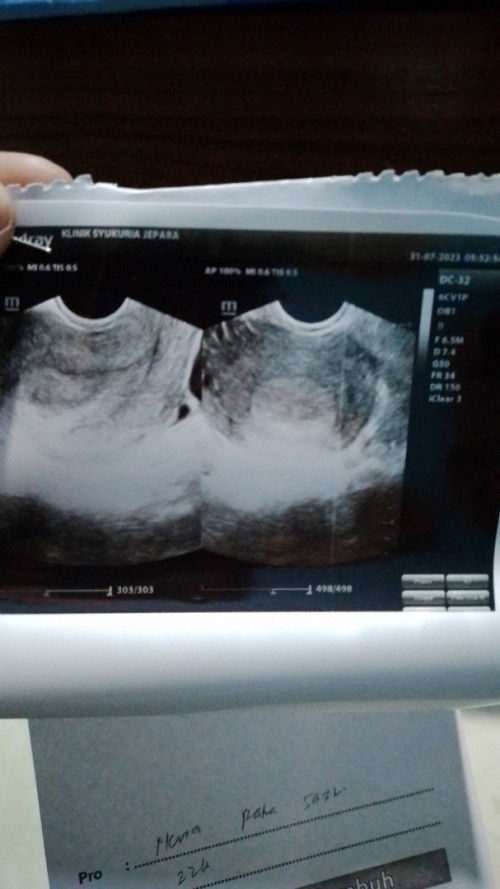

Bun ini USG pertama kali aku kata dokternya blm kelihatan apa",apa bener ini penebalan dinding rahim

iya benar,. aku wktu itu jga gtu bund, usg umur 6 mnggu (mnrut hpht) mash penebalan dinding rahim, tapi ada kantongnya kecil bgt,. kta dokter itu baru awal kehamilan sktr 4mngguan... wktu itu untuk memastikan benar kantong atau bukan sma dokternya aku di cek pake transval, dan benar itu kntong bund, alhamdulillah skrg udh 6 mnggu jalan 7,. sehat selalu hingga lahir amiin

Baca lagiAku juga kayak gitu Bun, pertama tespack positif lngsung USG, tapi belum kelihatan apa", hanya penebalan dinding rahim. Akhirnya di suruh balik lagi 2 Minggu kemudian, tapi pas udah 2 Minggu saya ke dokter kandungan yang lain. Pas USG Alhamdulillah udah ada kantung dan janinnya bahkan udah ada Djj nya Bun. jadi tunggu 2 minggu-3 Minggu lagi yah Bun. semangat bunda

aku juga smlm udh USG tv penebalan dinding rahim Bun, suruh balik 3 Minggu lagi. dikasih obat dan penguat kandungan

usg transvaginal aja ka lebih jelas